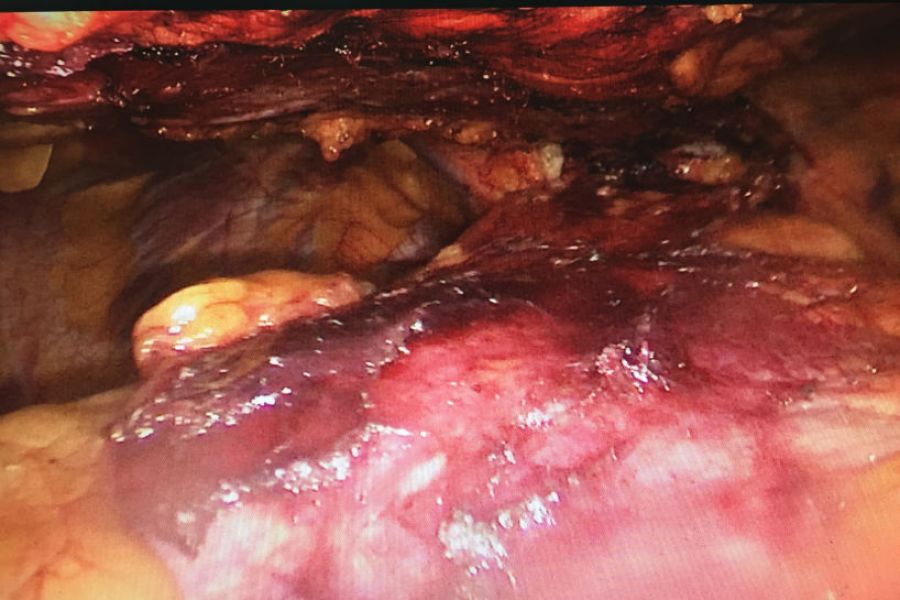

患者王某某40岁,因右胸阵发性疼痛1年入住我院疼痛科,检查发现前上纵膈肿瘤。经心胸外科钟强主治医师会诊后转入心胸外科。转入后予积极完善相关检查,排除相关禁忌症,考虑患者年轻,对创伤小、美观等要求,经研究决定予行胸腔手术。手术入路选择经剑突下切口,黄勇科主任及向加树副主任临场指导,术中杨智杰副主任医师、张建军主治医师及左选健住院医师密切配合,仔细解剖,历经2小时手术完整切除肿瘤。术后患者无明显并发症,主诉疼痛感轻,恢复良好。

纵膈肿瘤术中情况